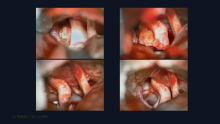

手术系列094:乙状窦后入路切除误诊为脑膜瘤的三叉神经鞘瘤

脑肿瘤-脑膜瘤

樊雁峰 关注

广东三九脑科医院昨天22:14 45阅读 0评论 1点赞 -